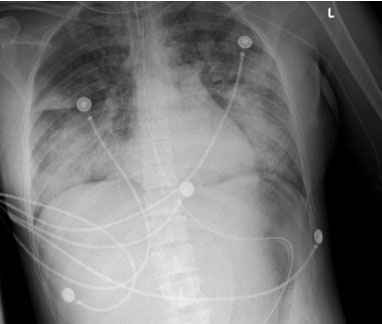

On HD3 chemotherapy was initiated and the patient developed acute respiratory distress (ARDS), requiring intubation and admission to the intensive care unit (ICU) (Figure 2). On HD5 she improved, was extubated, and discharged from the ICU. She continued routine APL treatment with antimicrobial prophylaxis. On HD13 her coagulopathy reversed and she was surgically cleared for termination of pregnancy with hemoglobin levels greater than 8 g/dL and platelets greater than 80,000 per µL. On HD14 the patient received mifepristone 200 mg orally once. On HD15 she received 600 mcg misoprostol buccal 2 hours prior to surgery. Dilation and evacuation was performed under ultrasound guidance. Paracervical injection of four units of vasopressin in 20 cc normal saline was performed at the start of the procedure. The estimated blood loss was 200 mL and no uterotonics were required. The patient received Doxycycline for preoperative prophylaxis and a gonorrhea/chlamydia swab was negative. Levonorgestrel IUD was placed under ultrasound guidance. Immediate and 2-week postoperative checks were unremarkable, and the patient continued with her APL treatment. The patient was contacted six months postoperatively and remained without complications.

Figure 2: Chest X-ray after intubation of the patient demonstrated extensive bilateral airspace disease consistent with ARDS.

This case is an example of newly diagnosed APL on ATRA-ATO and hydroxyurea, complicated by coagulopathy, differentiation syndrome, and neutropenia, that underwent uncomplicated D&E with LNG-IUD placement. The dysfunctionality of the coagulation system is a common complication of APL that poses an increased risk of early mortality by hemorrhage or thrombosis. Coagulopathy for this patient was likely due to underlying leukemia, differentiation syndrome, and/or concomitant chemotherapy increasing the risk for the development of ARDS. The surgery took place after coagulopathy was reversed and differentiation syndrome had improved; however, the patient was still neutropenic at the time. During the postoperative course, the patient showed no signs of pelvic infection or heavy vaginal bleeding.